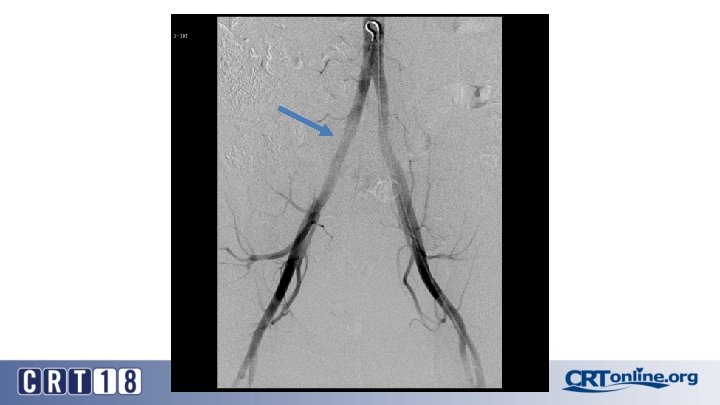

Blue Toe Syndrome

Returns Next day

Failed recanalization: BKA